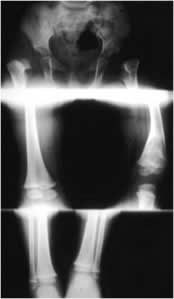

Fig 102. Longitud de extremidades.

A: Rx simple con 3 disparos en las articulaciones, en una misma película.

B: Telemétrica de miembros inferiores.

C: Escanigrama de TAC.